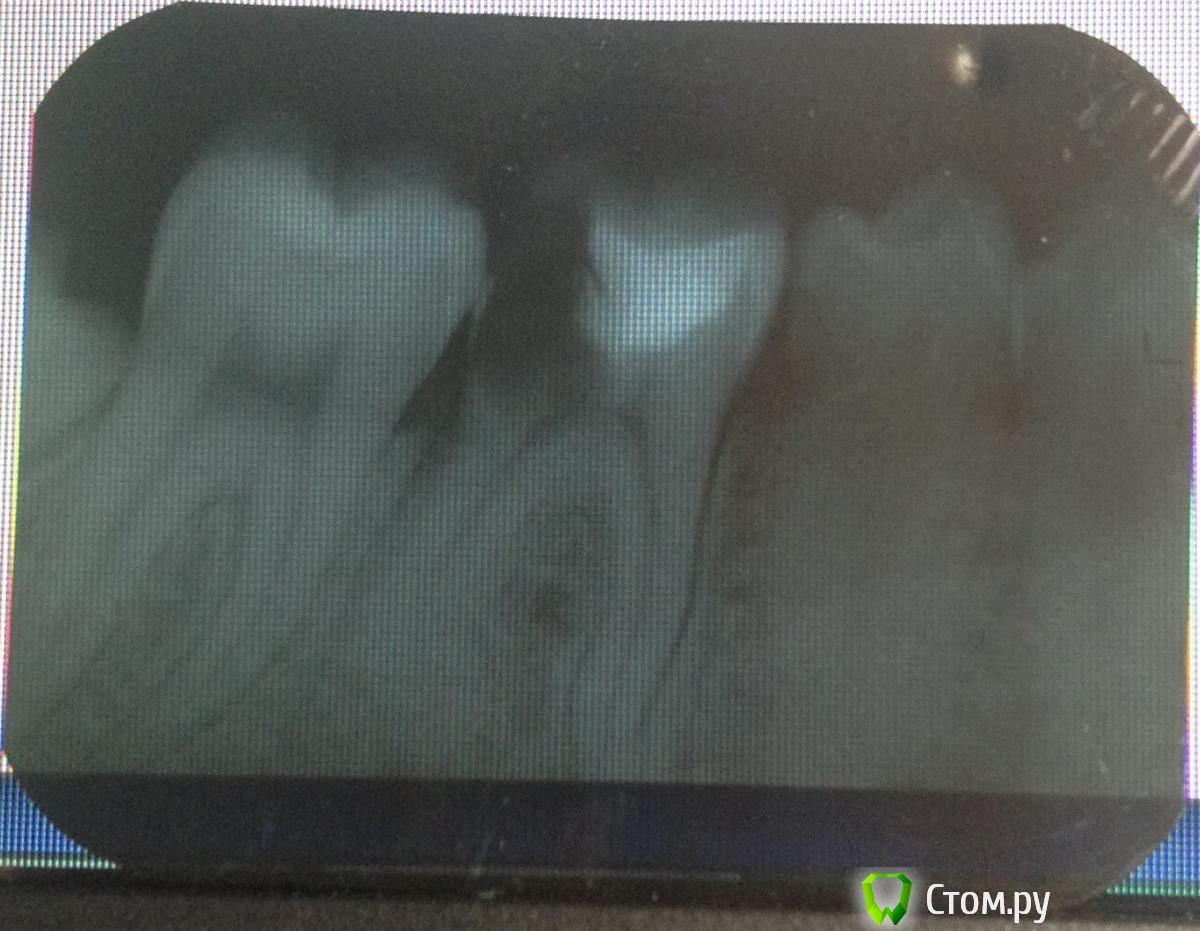

and13 Опубликовано 3 июня, 2014 Автор Поделиться Опубликовано 3 июня, 2014 сделал еще один снимок. четко видно корни врач говорит что очень сложное тут удаление, корни все кривые. она так же предложила залить каналы спец веществом-лекарством, все это дело запломбировать и оставить так. говорит может года на 3 хватит что думаете по этому поводу? Ссылка на комментарий

IvanK Опубликовано 3 июня, 2014 Поделиться Опубликовано 3 июня, 2014 Ищите Врача, для которого не сложно 1 Ссылка на комментарий

faity Опубликовано 3 июня, 2014 Поделиться Опубликовано 3 июня, 2014 в удалении этого зуба нет ничего сложного, восьмерка сложнее удаляться будет скорее всего. сохранять не стоит, за 3 года уйдет кость и имплантация с аугментацией выйдет минимум в 2 раза дороже, чем просто имплант сейчас Ссылка на комментарий